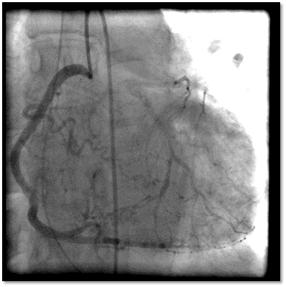

A 41-year-old Asian woman was presented with out-of-hospital cardiac arrest. As she was in a musical concert, she presented a sudden cardiac arrest (SCA), she had immediate chest compression by attending first-aid workers, with a no-flow of less than 2 minutes. Spontaneous circulation was restored after 4 minutes of cardiopulmonary resuscitation and 2 electric shocks. Hemodynamics was stable with no need for inotropic support and electrocardiogram showed sinus tachycardia without repolarization abnormalities. At hospital admission, the scan eliminated recent intracerebral bleeding and pulmonary embolism. Then a coronary angiogram revealed a chronic total occlusion of the ostial left main trunk with complete collateralization by the right coronary artery (Figure 1) (videos in supplemental material). The echocardiography showed no impairment in the left and right systolic function. After review, the CT scan showed increased thickness of the aortic wall of the thoracic aorta extended to the arch branches (Figure 2).

Figure 1: Coronary angiogram (right view) showing chronic total occlusion of the ostium of the left main stem (arrow) with an ectasic proximal circumflex with a Rentrop 3 collateralization by the right coronary artery.